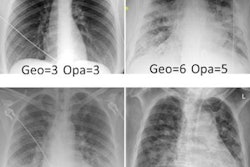

Exemplary bedside chest radiograph in which the initial grading of specific imaging findings by the physicians in the intensive care unit (nonradiologist) was not aligned with the grading by the experienced radiologists (majority vote) in an 85-year-old woman after pacemaker implantation for atrioventricular block 3. L = left patient side, R = right patient side. Image courtesy of Radiology.Next, a separate internal test set of 100 radiographs from 100 patients was assessed independently by a panel of six radiologists to establish ground truth for each exam. The team then used the kappa measure to compare these individual assessments, as well as those rendered by two ICU nonradiologist physicians using the neural network and by the neural network alone.